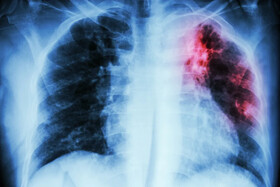

بیماری سل یک بیماری عفونی واگیردار میباشد که توسط میکروب سل ایجاد میشود. سل میتواند تمام ارگان های بدن را درگیر نماید، ولی بیشتر ریهها را آلوده میکند و از طریق هوا قابل انتقال است.

سِل یک بیماری عفونی شایع و در بسیاری از موارد مرگبار و کشنده است که با گونههای مختلف مایکوباکتریا و به طور معمول «مایکوباکتریوم توبرکلوزیس» ایجاد میشود و انتقال باکتری توسط قطرکهای تنفسی از فرد بیمار است؛ عوامل متعددی مردم را در ابتلا به عفونت سل مستعدتر میکند و مهمترین عامل خطرساز در سراسر جهان اچآیوی است و همچنین سل به ازدحام بیش از حد و تغذیه نامناسب بسیار مرتبط است که باعث میشود یکی از بیماریهای اصلی در اثر فقر باشد.